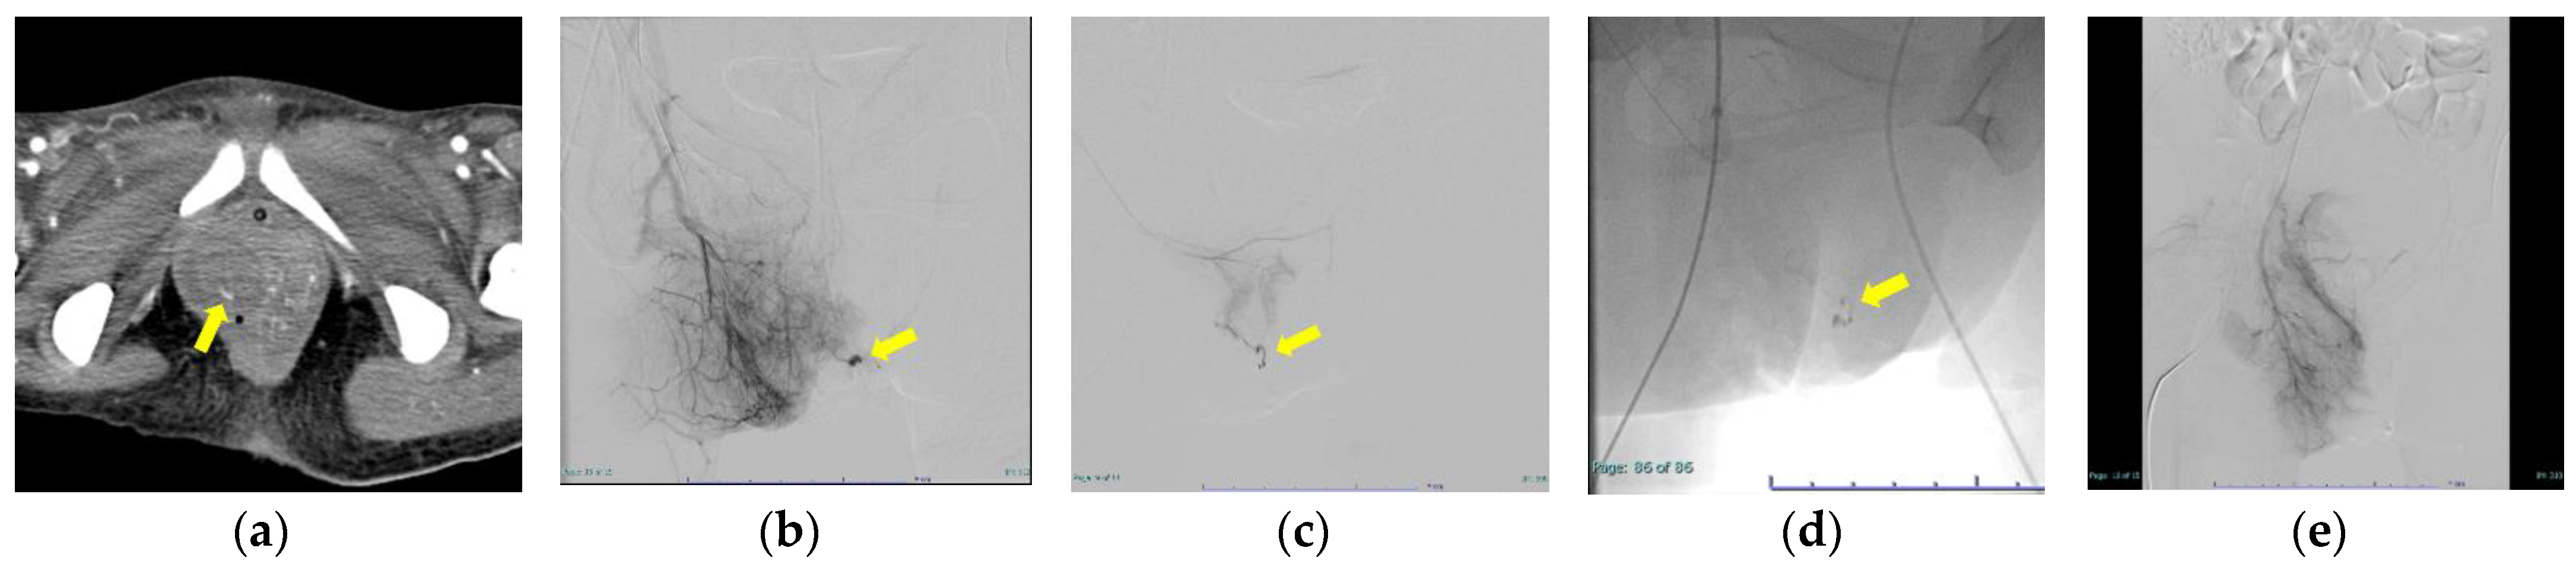

| 1 | 28 | 18.5 | 31/0 | primiparity | induction of labor | own | 1426 | 6300 | 1.06 | 64.7 | 1.13 | 171 | RBC20U, FFP22U, cryoprecipitate8U | Chronic myeloid leukemia | operative hemostasis | right internal pudendal artery branch (NBCA:lipodol = 1:4) 0.3 mL bilateral uterine artery (gelatin sponge) |